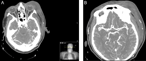

Anaplasic astrocytoma with exophytic growth in Sylvian fissure in a pediatric patient: a case report

José Raúl Guerra-Mora and others

Journal of Surgical Case Reports, Volume 2018, Issue 4, April 2018, rjy079, https://doi.org/10.1093/jscr/rjy079